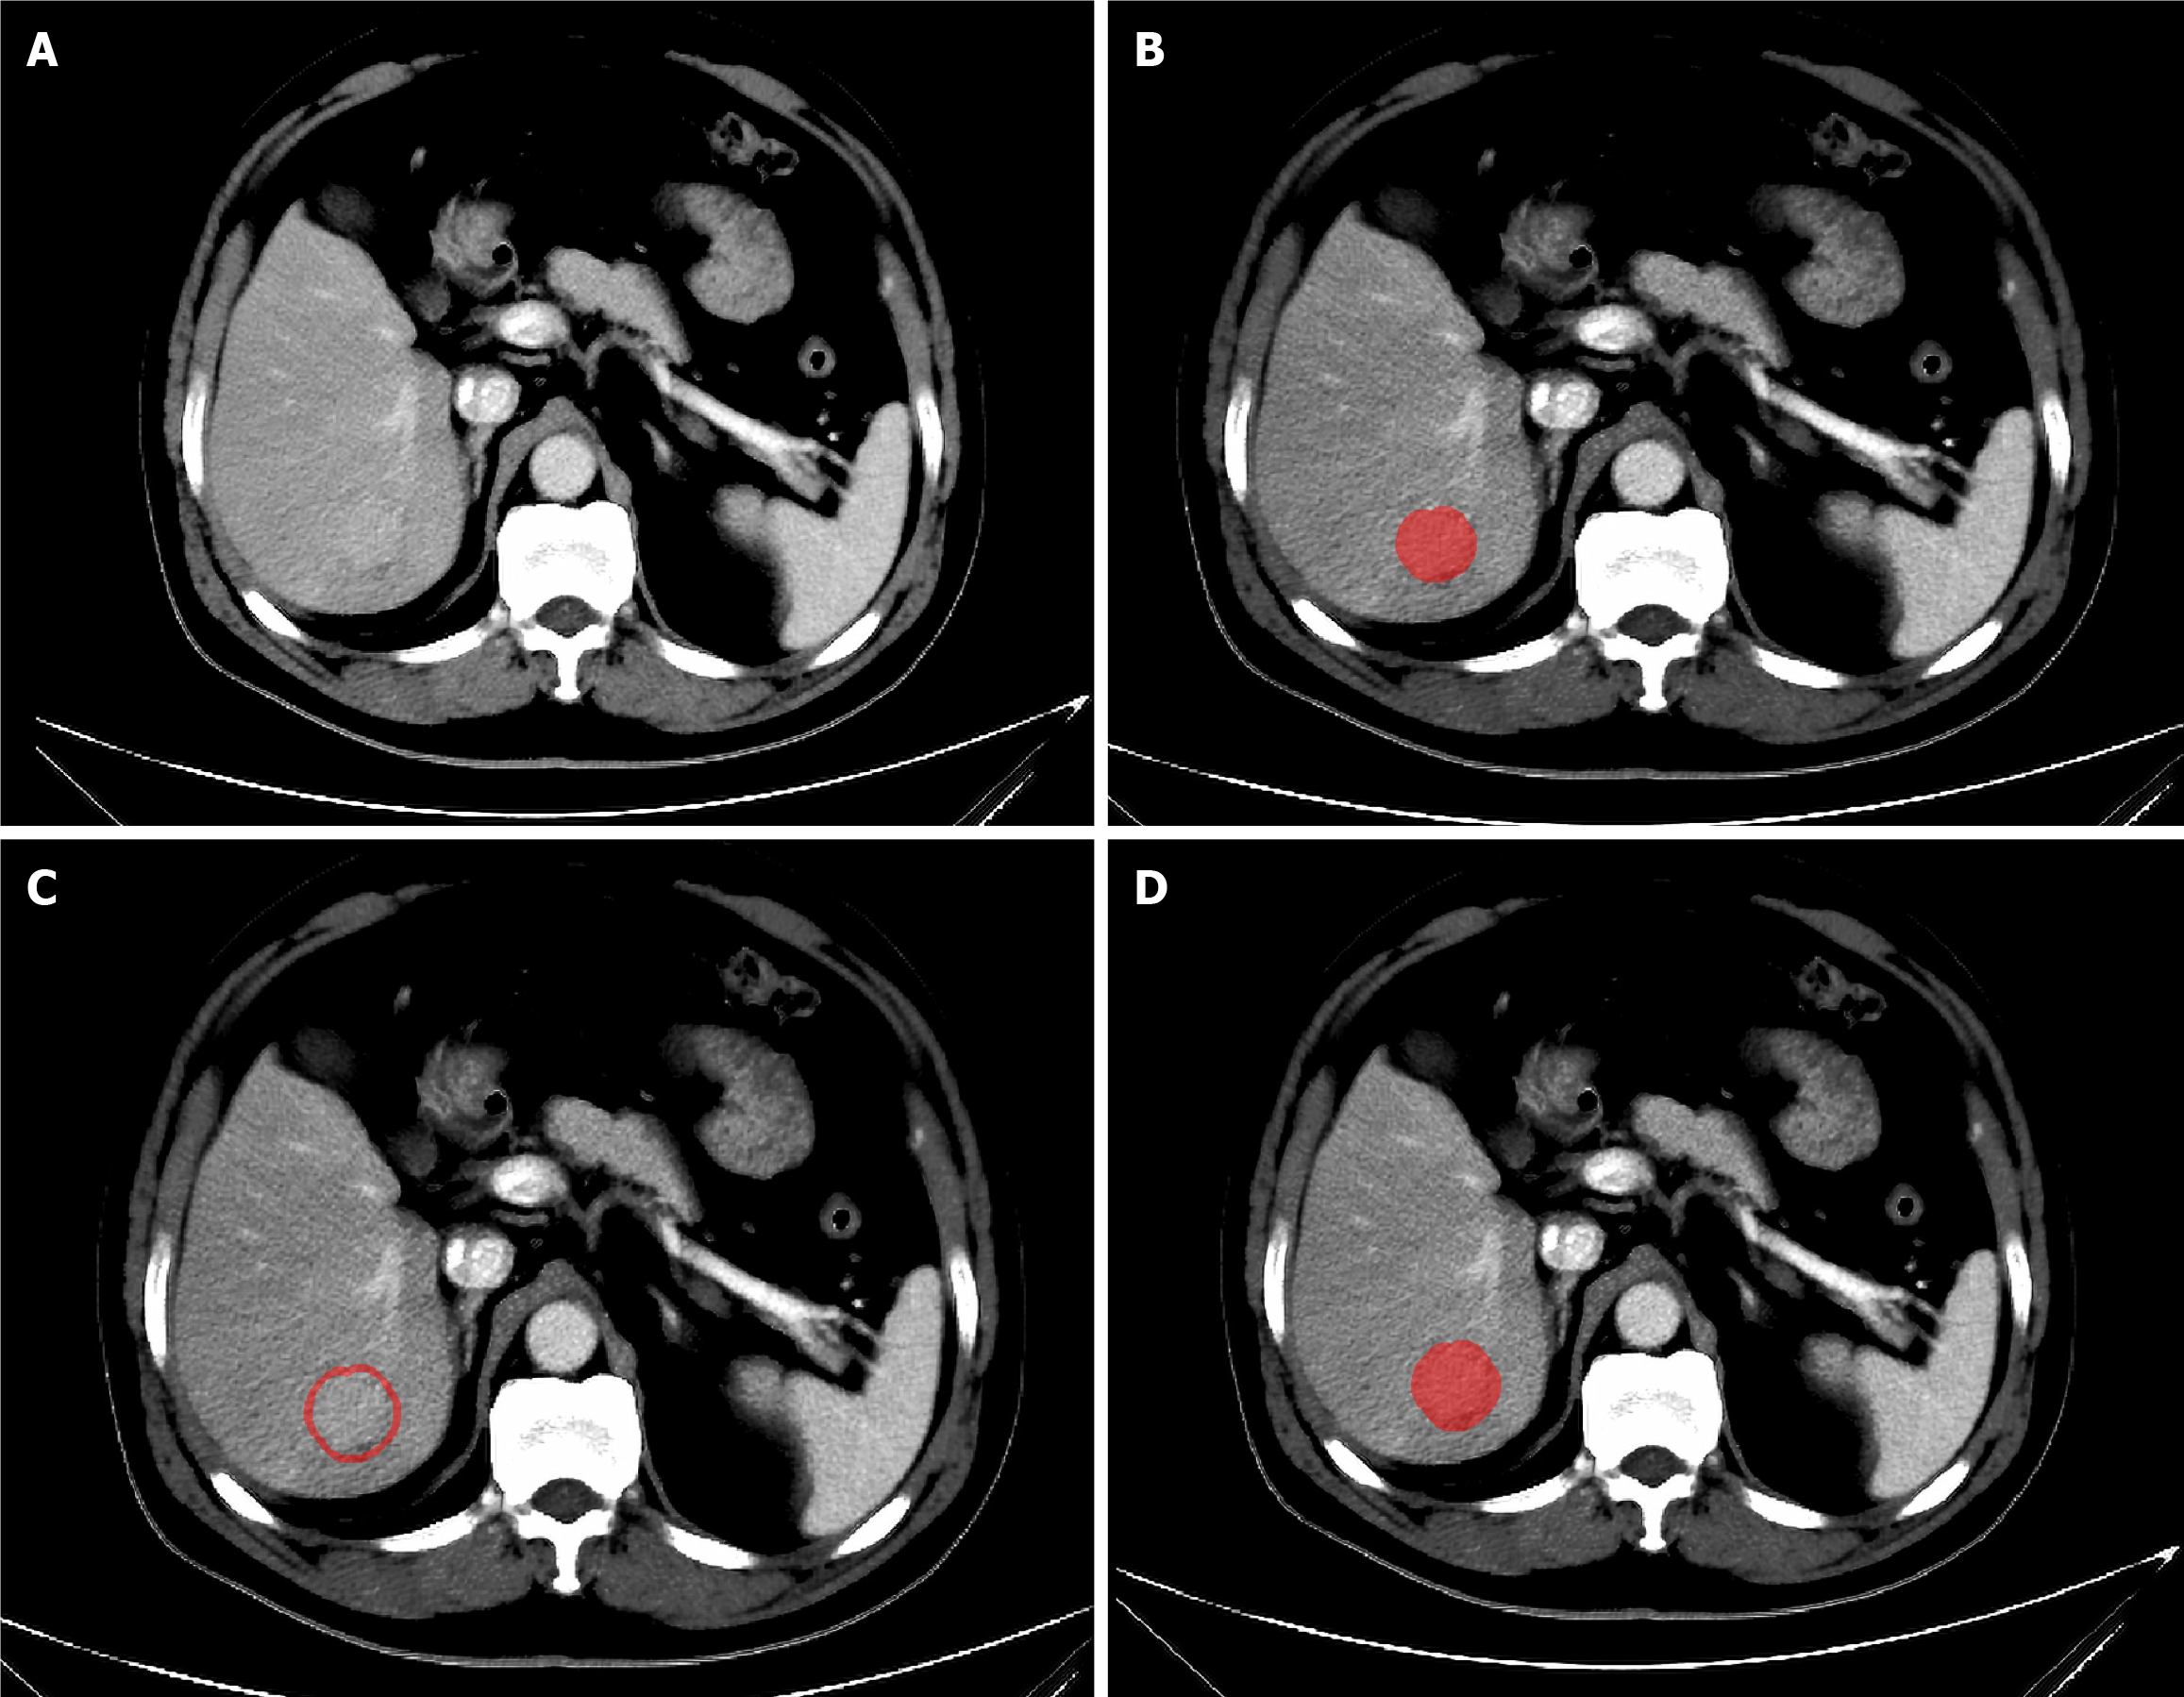

The volume of interest (VOI) is manually delineated on portal venous phase images by a doctor with extensive experience in reading abdominal CT images with ITK-SNAP software (version 3.8.0)[17]. Initially, manual delineation is performed layer by layer along the lesion’s edge in the cross-sectional view to form the VOI. Then, a three-dimensional expansion algorithm in Python software is used to automatically expand the VOI, with manual elimination of areas extending beyond the liver tissue. Zhao et al[18] constructed different prediction models using different sizes of peritumoral regions and reported that the 3-mm peritumoral model had better predictive performance than other regional prediction models. Therefore, in this study, the area within 3 mm around the tumour was defined as the peritumoral region. The VOI within the tumour was removed from the expanded VOI to obtain the peritumoral VOI, as shown in Figure 3. Thus, each patient had three different types of VOIs (intratumoral, peritumoral, and merged VOIs). Subsequently, the CT images of 30 patients were randomly selected, and the VOI was redrawn by the same doctor one month later to assess intraobserver reproducibility. Another senior doctor delineated the VOI on these images to evaluate interobserver reproducibility.